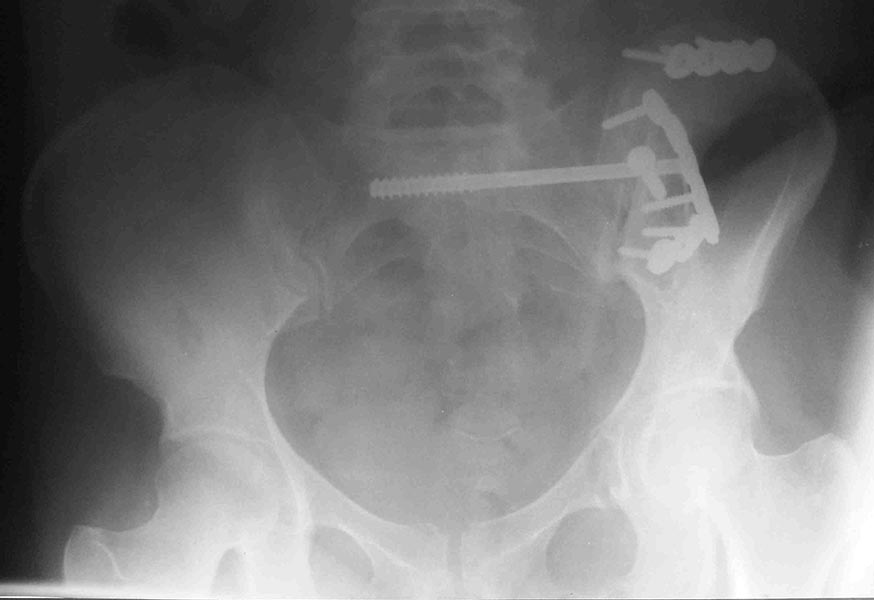

Здесь примеры фиксации с различными вариантами.... .

Здесь снимки, которые показывают направление стержня, а также идею репозиции вытяжением. На рентгенопроницаемых столах имеется возможность установить дополнительную раму, где по желанию можно увеличить или уменьшить высоту угла вытяжения. Для репозиции таза больной в положение на спине, стержень для вытяжения остается во время операции. Система подойдет для тракции головки бедра из вертлужной впадины, и для этого стерильная веревка и Synthes Universal Chuck with T-Handle.

Двухстороннее повреждение крестца и травматическая ампутация бедра, где неопытной бригадой дежурантов установлен верхний наружный фиксатор для стабилизации. На третий день ревизия на более стабильный, и окончательная фиксация. Первые снимки после стабилизации таза, и другие, где показаны (параллельные) правильная установка на AIIS т.е на месте прикрепления прямой мышцы бедра. Ампутация закончена костно пластическим методом.